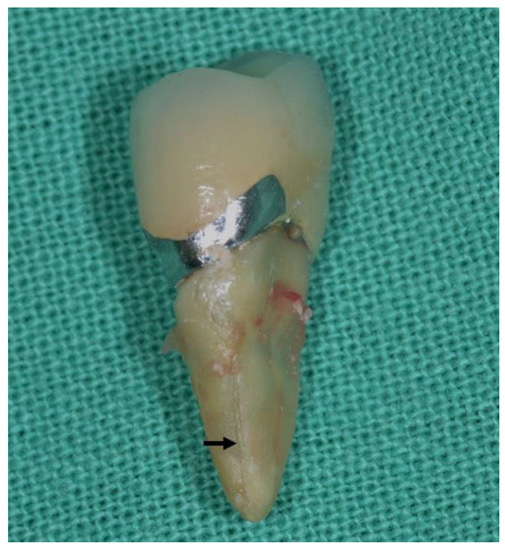

6.7. Exploratory Surgery

9.1. Displacement of Fractured Fragment

10. Treatment and Prevention of VRFs